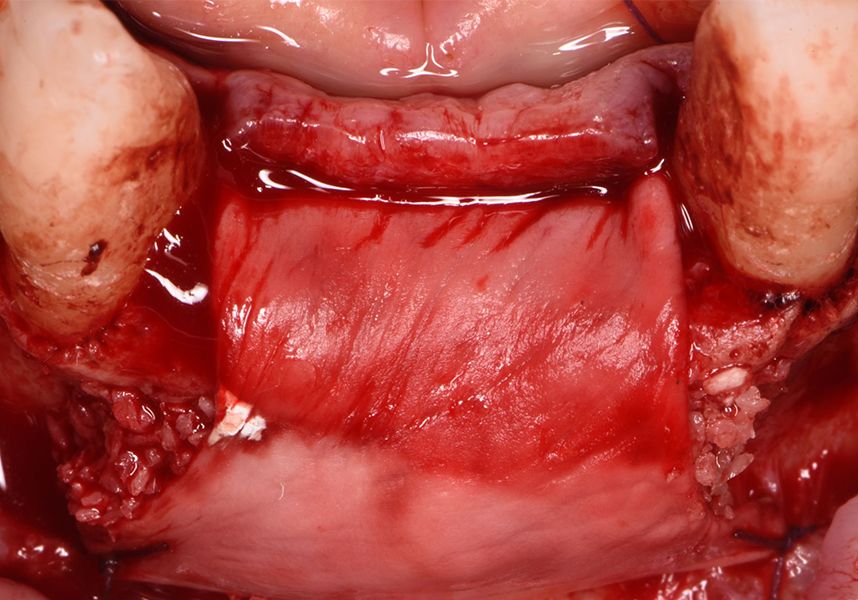

The membrane was sutured with PGA reabsorbable suture to the periosteum to secure it, thus avoiding subsequent reentry to remove fixings such as tacks.

After a post-operative period without complications, the healing abutments were fitted in a second surgical stage 5 months later. Six months after implant placement, the final metal-ceramic prosthetic restoration was loaded.